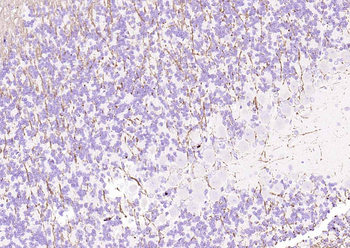

Paraformaldehyde-fixed, paraffin embedded (human brain), Antigen retrieval by boiling in sodium citrate buffer (pH6.0) for 15 min, Block endogenous peroxidase by 3% hydrogen peroxide for 20 minutes, Blocking buffer (normal goat serum) at 37°C for 30 min, Antibody incubation with (MBP) Polyclonal Antibody, Unconjugated (orb783422) at 1:200 overnight at 4°C, followed by operating according to SP Kit (Rabbit) instructionsand DAB staining.